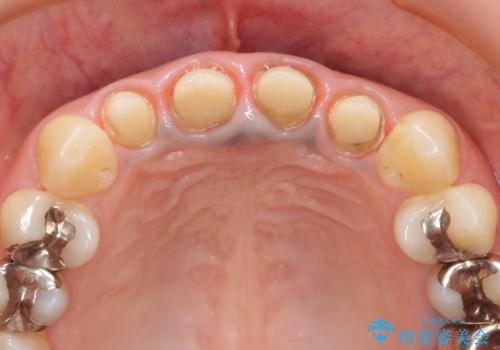

ファイバーコア・セラミッククラウンは金属を用いない審美的な治療法です。

- 44万円(エコノミークラウン×4・ファイバーコア×4・仮歯×4)費用は治療当時の料金となります